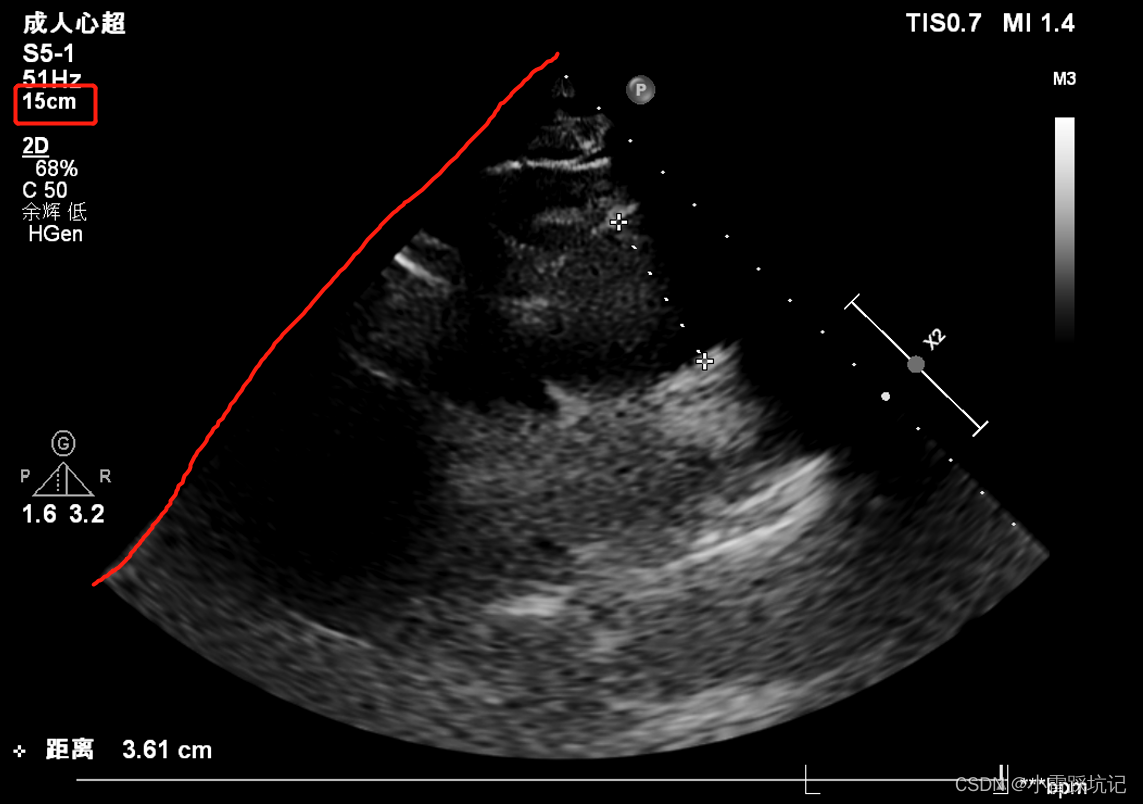

但是很奇怪的是图像中很明确的告诉测量值 15cm,意味着这条红线是15cm.